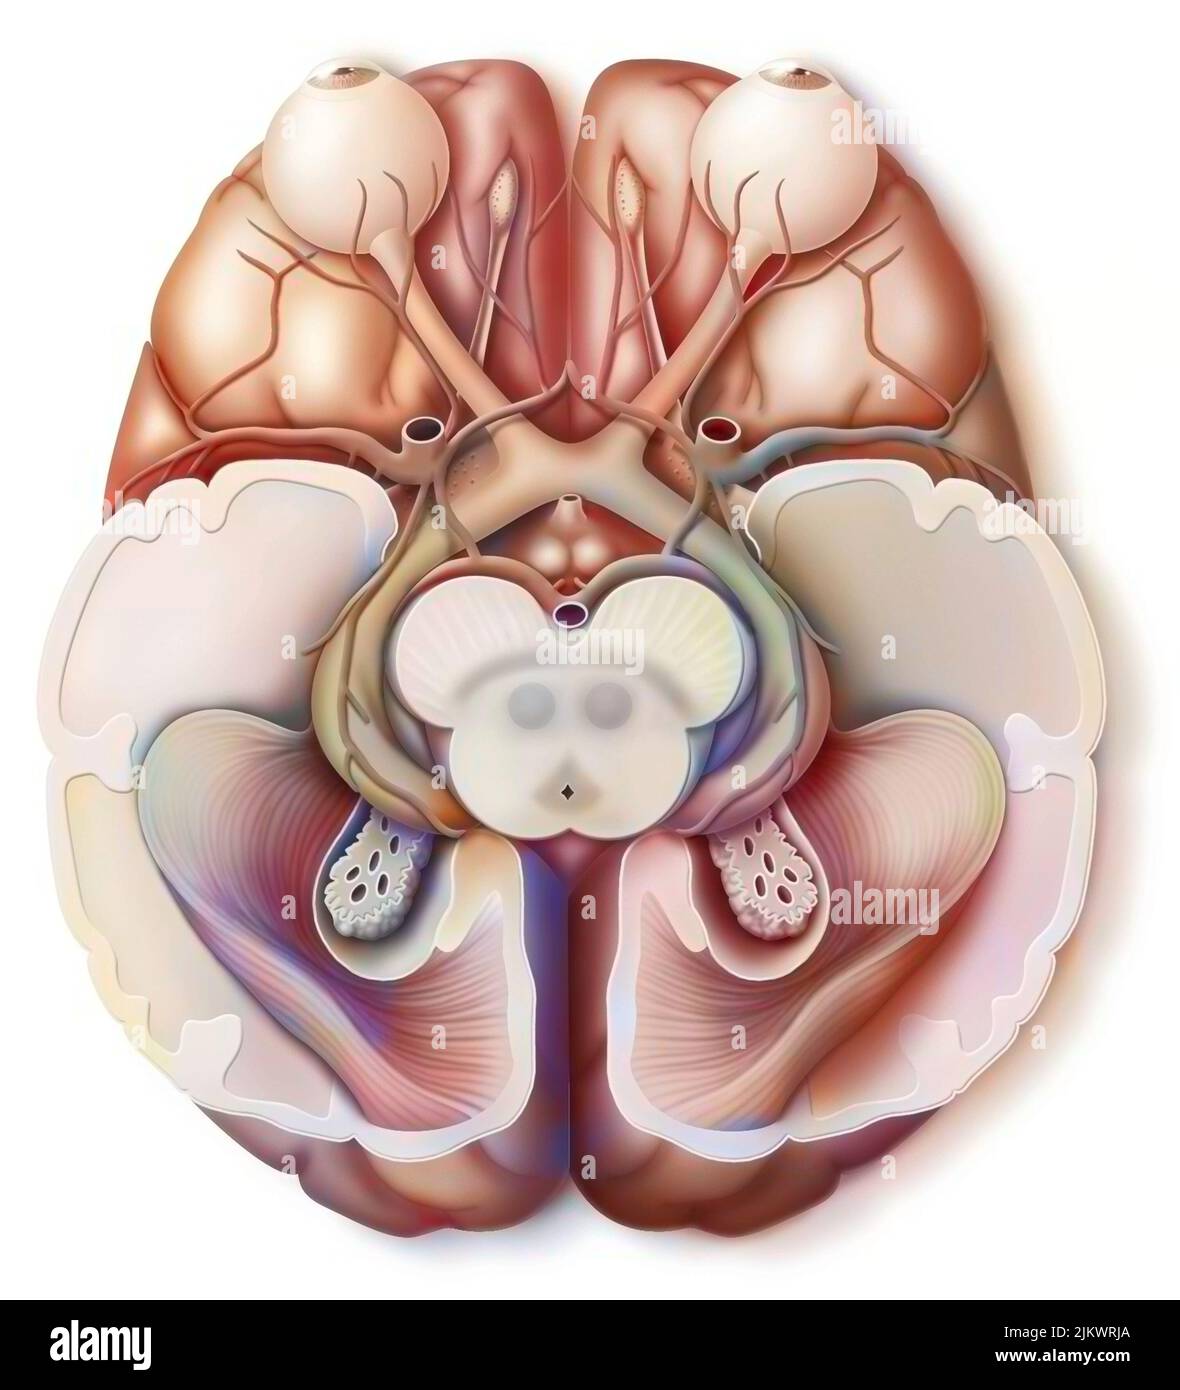

RF2JKWPG7–Troisième étape dans la façon dont le cerveau fonctionne quand vous tombez amoureux: La prise de décision.

RF2JKWPG3–Cerveau dans le chimpanzé avec ses zones (cognitives, auditives, visuelles) et cortex (moteurs, sensoriels).